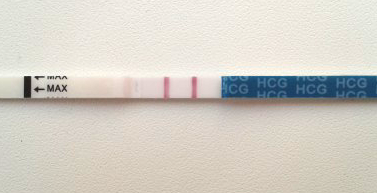

Девочки, это беременность)

Следующее фото вчерашнего теста на беременность.

Получается, что получается... Ну, чтож, вырастим)

Не, это на 9 дпо, подруга говорит у тебя двойня наверно))))))

Это у нас 9 дпо, двойня там что-ли? ))))

Не, 9 дпо, все вокруг говорят что двойня))))))))))

Поздравляю!!!😀 По этому наверное такие яркие на 9 день, ХГЧ скакнул)